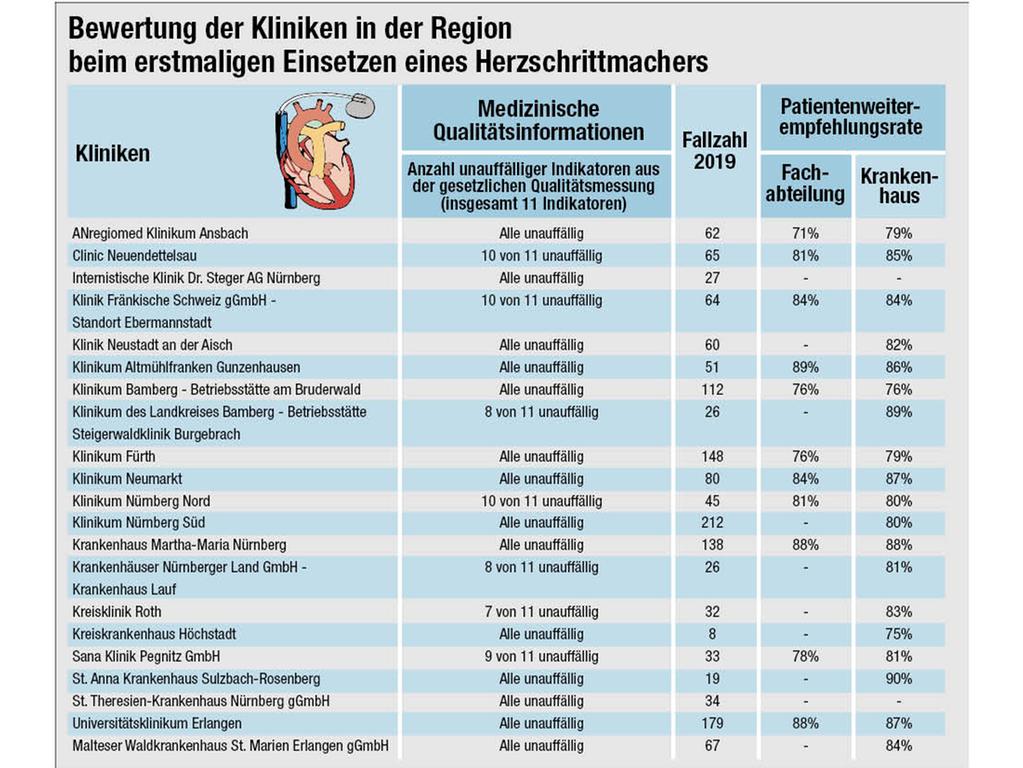

Herzrhythmusstörungen sind mit steigendem Lebensalter eine Volkskrankheit. Manchen Betroffenen ist mit einem Rhythmus-Implantat geholfen: einem Herzschrittmacher oder auch, seltener, mit einem implantierbaren Defibrillator. Bei stationär durchgeführten Herzschrittmacher-OPs erzielen viele Kardiologie-Abteilungen der nordbayerischen Krankenhäuser sehr gute Ergebnisse. Das Nürnberger Krankenhaus Martha-Maria führt in unserem Datenprojekt NN/NZ-Klinikcheck die Liste von 19 Häusern an, gefolgt vom Universitätsklinikum Erlangen und dem Klinikum Neumarkt.

Um die Grafik in voller Auflösung zu sehen, klicken Sie bitte hier.

Um die Grafik in voller Auflösung zu sehen, klicken Sie bitte hier.

Welche Qualitätskriterien liegen dem Klinikcheck zugrunde, und warum erfüllt das Krankenhaus Martha-Maria sie so gut?

Es schlägt sich positiv nieder, wenn die Dauer des Eingriffs kurz bleibt und die Röntgenstrahlenbelastung gering ist. Geprüft wird auch, ob die Entscheidung zum Schrittmacher gerechtfertigt war und ob der geeignete Gerätetyp ausgewählt wurde. Komplikationen durch verrutschte Sonden, Blutergüsse, Entzündungen sowie vermeidbare Folgeeingriffe müssen möglichst selten bleiben.

Martha-Maria setzt dabei auf erfahrene Implanteure und, für Pohle ebenso wichtig, auf ausgiebige Beratung und Untersuchung in der Spezialsprechstunde für Herzrhythmusstörungen. "Wir führen auch eine konsequente Nachsorge durch", sagt der Chefarzt, dessen Abteilung jährlich insgesamt etwa 380 Schrittmacher-Eingriffe durchführt. Bei der Patientenzufriedenheitsrate liegt die Kardiologie des Diakonie-Hauses vergleichsweise weit vorn.